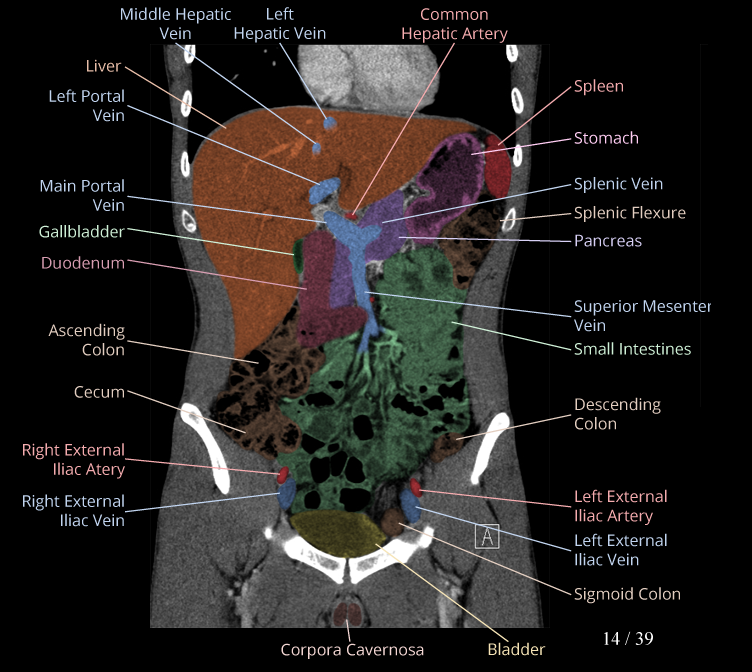

Body

Covers abdominal CT anatomy.